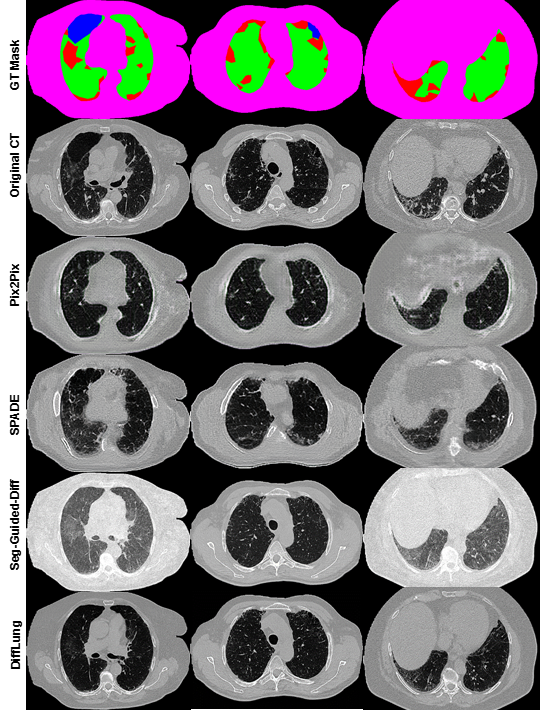

We conducted a quantitative evaluation of our model, DiffLung with the CBMAT algorithm, comparing it against other segmentation-guided methods, including the mask-ablated approach and GAN-based architectures such as Pix2Pix [15] and SPADE GAN [16]. Given the importance of capturing fine details in medical imaging, we chose Structural Similarity Index Measure (SSIM) and Peak Signal-to-Noise Ratio (PSNR) as our evaluation metrics [17], as they are well-suited for assessing image quality in terms of structural accuracy and noise level. SSIM evaluates structural similarity between images, while PSNR measures the fidelity of image reconstruction, both critical for medical image generation. Our model outperformed other methods, as shown in the table below, achieving higher SSIM and PSNR scores, which indicates superior quality in preserving anatomical details and reducing noise. These results demonstrate the effectiveness of DiffLung with CBMAT in generating realistic and diverse pathological textures compared to traditional GAN-based models.

It is worth noting that the DiffLung model was trained using the same database as for the training the segmentation model. While this choice was imposed by the availability of the annotated data at our hand, we believe that the highly imbalanced lung tissue classes, even partially compensated by the CBMAT strategy, has limited the performance of the generative models (especially for emphysema, as seen in Fig. 1). Also, having unifying fibrosis and ground glass in a single ILD class will restrict the distinction of these patterns in the generated images. Future work will consider increasing the training dataset of the DiffLung model by including new samples of less represented classes, mainly emphysema, and separating the ILD class into fibrosis and ground glass.